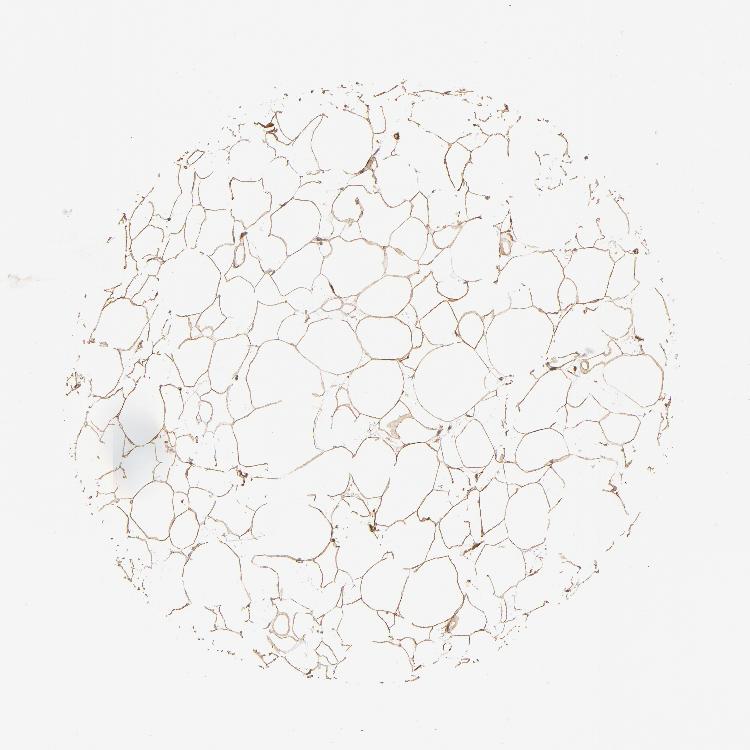

SOFT TISSUE 1 - Antibody stainingi

Antibody staining in the annotated cell types in the current human tissue is reported as not detected, low, medium, or high, based on conventional immunohistochemistry profiling in selected tissues. This score is based on the combination of the staining intensity and fraction of stained cells.

Each image is clickable and will lead to virtual microscopy that enables deeper exploration of all samples and also displays staining intensity scores, fraction scores and subcellular localization as well as patient and tissue information for each sample.

Antibody HPA002116

Chondrocytes Low

Fibroblasts Medium